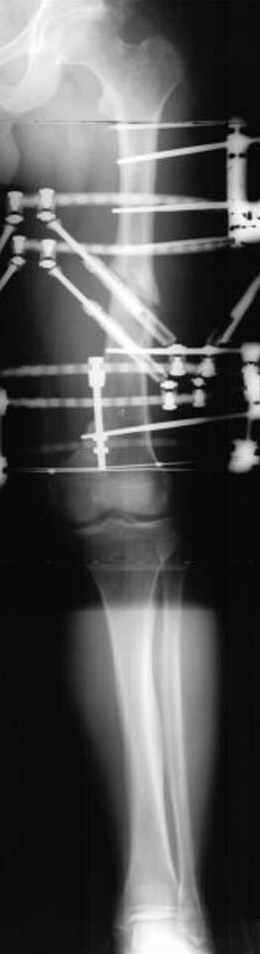

Отправитель: Djoldas Kuldjanov 23 Ноябрь 2004, 18:21

пластическая модель; и коррекция бедра аппаратом Илизарова.

Несколько снимков из моей коллекции, чтобы разьяснить, почему мы до сих пор делаем различные варианты остеотомии.

На рисунке N1 предоперационный план лечения ложного сустава шейки бедра- линия ложного сустава, угол и направление введения импланта, клиновидная остеотомия в градусах и миллиметрах, второй снимок после коррекции, расчет, на сколько удлиняется конечность и размеры импланта;

N3 рисунок окончательный снимок, после операции моя рентгенограмма должен выглядеть примерно как эта картина. На N4 снимке клин перед удалением; N5 послеоперации 3 нед.; N6 окончательная рентгенограмма.